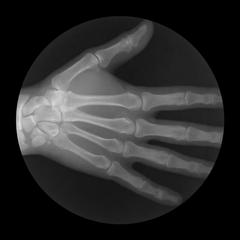

右手X光下的抓握动作